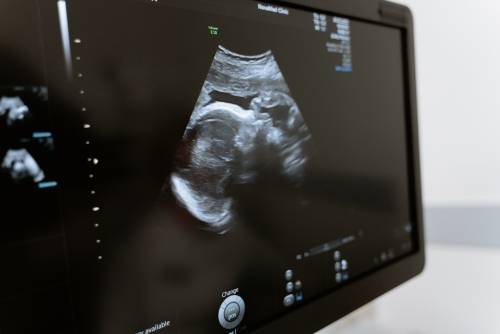

超声介入检查心脏,通常是指通过心脏腔内超声检查来诊断心脏疾病的方法。检查时需要放置引导管进入心脏,然后通过显示器观察心脏的结构、血流情况,以及是否存在异常病变等。 1、心脏结构:可以清楚显示先天性心脏